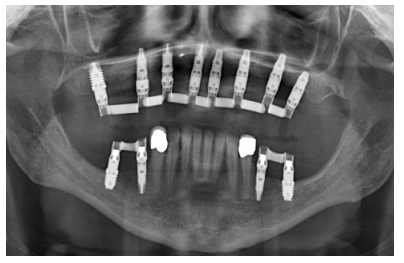

Cuatro meses después de la cirugía inicial de regeneración del maxilar se lleva a cabo un nuevo Cone-beam dental, en el que se planifica la siguiente fase de la cirugía en función de la ganancia ósea que se ha logrado con los injertos en bloque y la técnica de Split en dos fases. En las imágenes podemos observar como en las zonas de máxima atrofia, donde se colocan los bloques se ha logrado una anchura que triplica la inicial (Figuras 19 y 20). En la apertura del colgajo se observa como las imágenes del TAC de planificación se corresponden con la realidad, y además que la zona tratada mediante Split en dos fases ha logrado también una anchura de cresta que ahora permite la retirada de los implantes transicionales y la inserción de nuevos implantes en esta posición, con una mejor situación de partida y eje para la confección posterior de la prótesis (Figuras 21-22). Se procede a la inserción de los implantes y se realiza una prótesis provisional de carga progresiva apoyada en los implantes colocados en la primera fase quirúrgica. De este modo, la paciente puede tener una prótesis fija sobre implantes que servirá para ir dando forma a los provisionales en cuanto a estética y función de cara a la prótesis definitiva (Figuras 23-24).

Cuatro meses después se procede a la carga de los implantes insertados en esta segunda fase quirúrgica. De nuevo se opta por unas segundas prótesis provisionales de carga progresiva, elaboradas del mismo modo que las anteriores Tres meses después la oclusión está preparada para la confección de la prótesis definitiva, por lo que se transforma la prótesis en una prótesis metal-cerámica, atornillada sobre transepitelial confeccionada mediante cad-cam (Figuras 25-26). La paciente ha recuperado la función demandada, así como la corrección de la oclusión de la prótesis completa, que presentaba una mordida cruzada lateral derecha con disminución de la dimensión vertical al inicio del tratamiento. La paciente acude a sus revisiones y el tratamiento se mantiene estable tal como se muestra en las imágenes tomadas a los 10 años de seguimiento (Figuras 27-28).